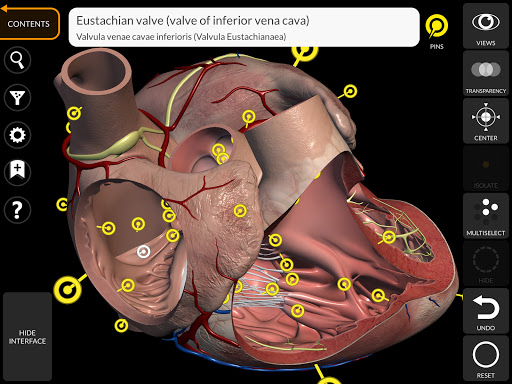

"Anatomy 3D Atlas" vous permet d'étudier l'anatomie humaine de manière simple et interactive.

Grâce à une interface simple et intuitive, il est possible d'observer chaque structure anatomique sous n'importe quel angle.

Les modèles anatomiques 3D sont particulièrement détaillés et avec des textures jusqu'à une résolution de 4k.

• Faites pivoter et zoomez chaque modèle dans l'espace 3D

• Option pour masquer ou isoler un ou plusieurs modèles sélectionnés

• En sélectionnant un modèle ou une épingle, le terme anatomique associé apparaît

• Fonction de transparence

• Les termes anatomiques peuvent être affichés en deux langues simultanément